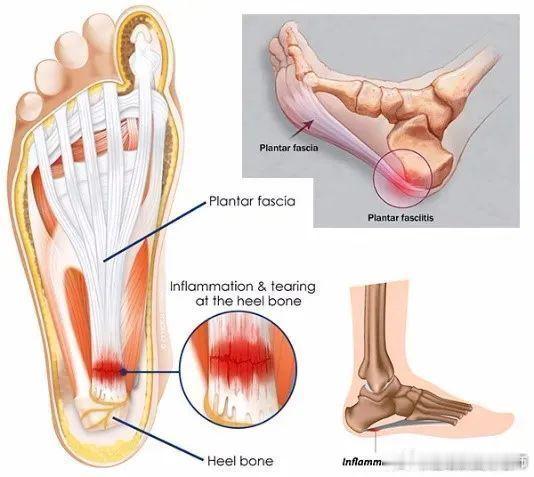

【足底筋膜炎原因】①小腿三头肌和跟腱的过度使用——我们小腿三头肌移形成跟腱,跟腱跨过跟骨和足底筋膜是移形存在的,所以张力也是共通的。

②下肢力线不正——很多人的足底筋膜疼痛,更多是脚内侧疼痛,很多人的踝关节是外翻的,足弓是塌陷的,在这种情况下,脚的内侧会承受一个更大的身体压力,内侧足底筋膜被牵拉,导致慢性损伤的疼痛。

【足底筋膜炎治疗禁忌】⚠️①不要过度刺激——足底筋膜炎其实是微细的软组织撕裂,如果我们再重的手法或剧烈的牵拉,对于重度足底筋膜炎来说,可能会产生二次损伤。